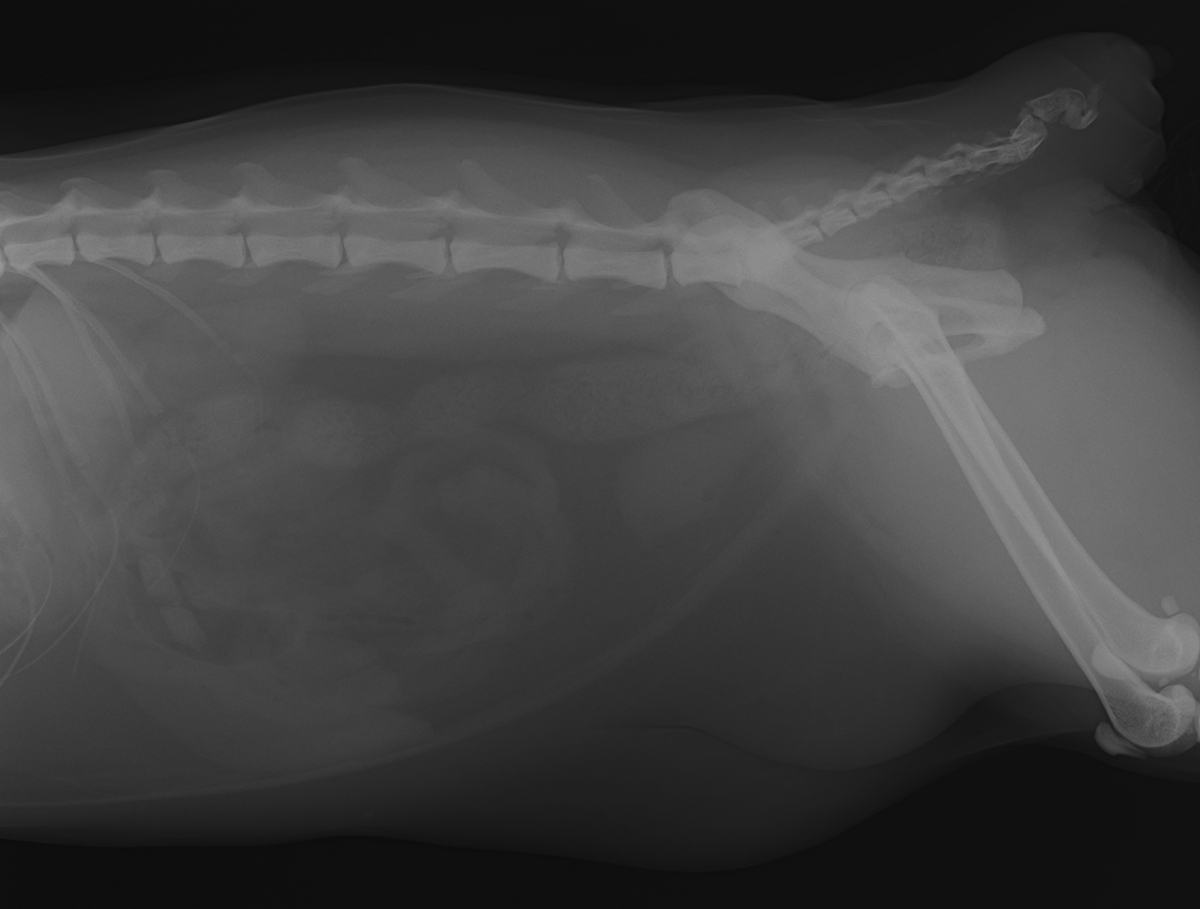

術後のレントゲンおよび結石の写真です。

結石成分検査の結果、『シュウ酸カルシウム』という成分でした。

シュウ酸カルシウム結石は食餌療法などで溶解・予防することが難しい結石であり、手術による摘出が必要となります。